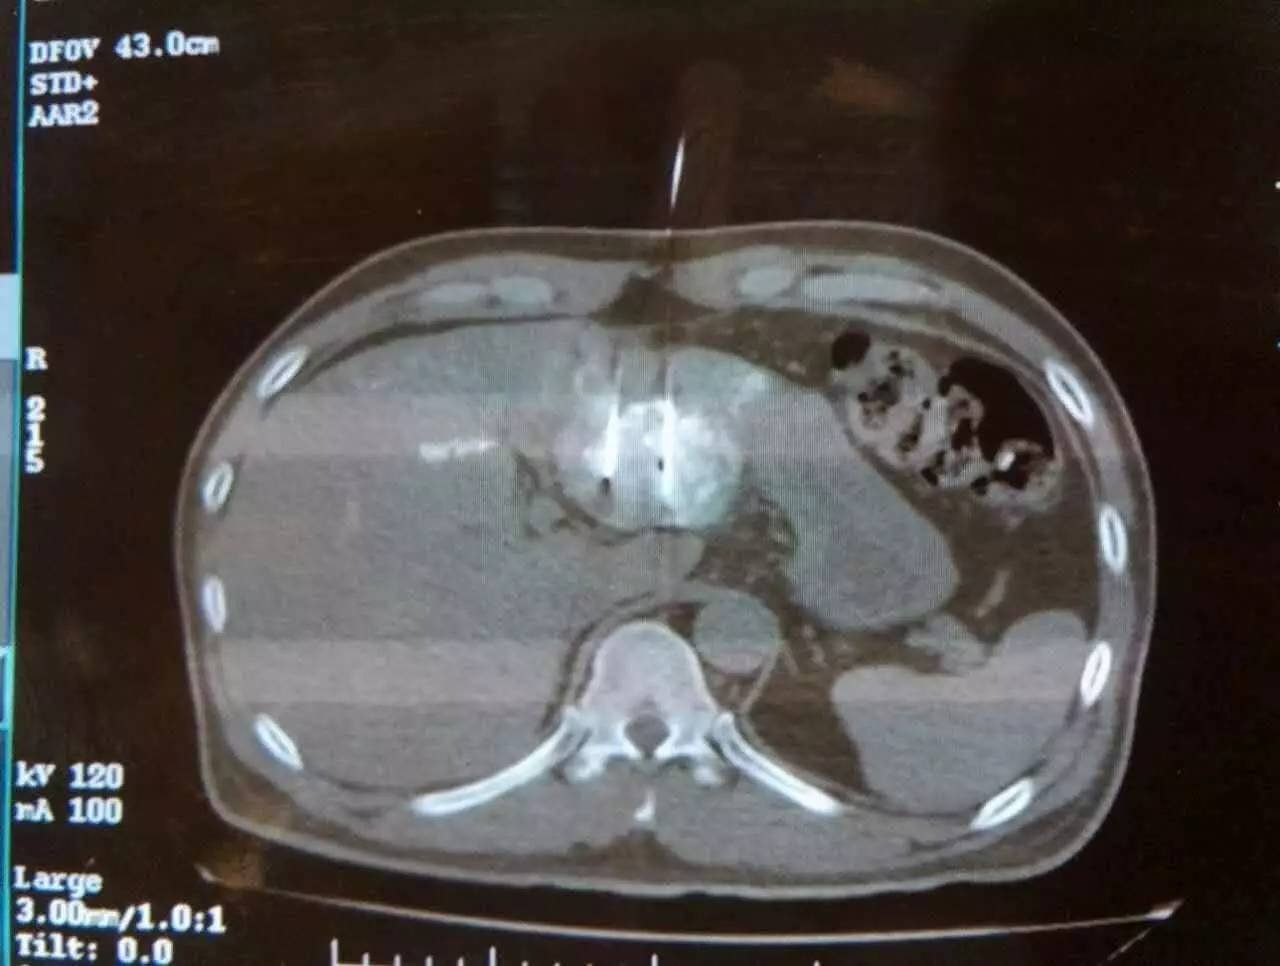

手术患者潘先生今年51岁,来自越南,今年7月在当地一次CT检查中发现肝左叶有一个4×4.3cm大小肿瘤,查血结果显示AFP665ng/ml。当地医生建议手术切除,潘先生拒绝了,随后在家自服中药。2016年11月11日,潘先生返院复查,CT和抽血结果分别显示:肝左叶肿瘤较前增大,AFP 1225ng/ml。病情有所恶化。

2016年11月19日,潘先生来到广州圣丹福医院,经细致检查,被确诊为原发性肝中分化肝表皮细胞癌Ⅱ期。此时,患者的肝左叶肿瘤已增至5cm,AFP达900ng/ml。

广州圣丹福医院手术专家白海山主任介绍,由于该患者是原发性肝癌,本可选择手术切除或常规消融手段,但采用这些方法所遇到的技术难点是:“患者的肝脏肿瘤毗邻重要脏器,左边与胃壁粘连,右边靠近肝部大血管,手术切除极有可能会伤及胃壁,导致胃穿孔等危险现象发生。同时,常规的消融手段难以消融彻底,难以达到根治性效果。”白海山主任表示。只好放弃。